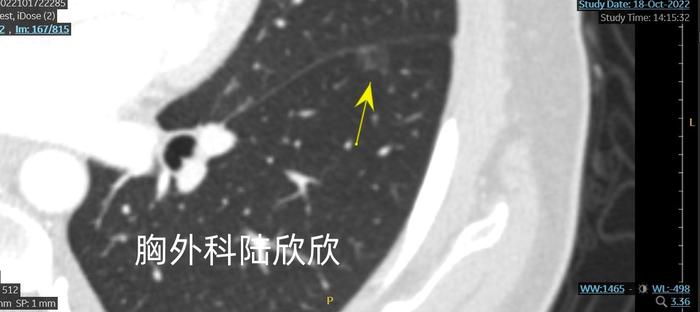

上图,左上肺的一个纯磨玻璃结节,位于胸膜下。看上去良恶性很难定。也有相当的可能是炎症。我在门诊和病人说:”这个纯磨玻璃结节密度偏高。总体看起来像是恶性的。感觉比较像是原位癌。”

住院后的薄层CT如下。

结节最大径5.4毫米。

我们可以看到,结节的腹侧有两个小静脉。背侧有一根小动脉。

上面两张图,结节内部最大的CT值,在两张薄层CT上分别是-393,-345。从CT值看,可能是微小浸润性腺癌。但是,我从总体上仍然判断可能是原位癌

同时做了胸腔镜下的左上肺楔形切除术。最终两个磨玻璃结节都是微小浸润性腺癌。我对左下肺的磨玻璃结节判断比较准确。对左上肺的磨玻璃结节判断有所偏差,真实病理是微小浸润性性腺癌,我判断是原位癌。